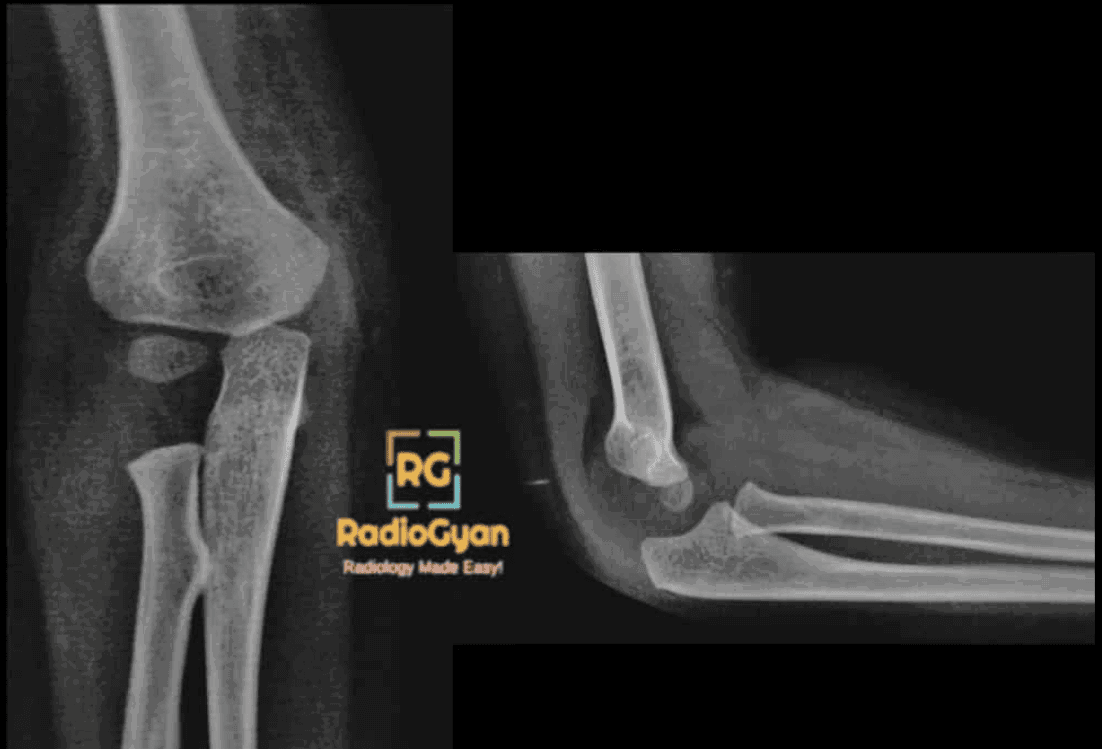

The fat pad sign is caused by intra-articular elbow joint effusion, often due to trauma resulting in an occult fracture of one or more bones around the elbow (e.g., radial head fracture in adults, supracondylar or condylar fractures in children).

A positive posterior fat pad sign on a lateral elbow radiograph is considered abnormal and indicative of intra-articular pathology, while the anterior fat pad may be normal or show a “sail sign” if elevated.

The sign is named for the displacement of the normally inconspicuous fat pads around the elbow joint visible on lateral radiographs. The anterior fat pad, when elevated, resembles a triangular sail (sail sign). The posterior fat pad, usually hidden within the olecranon fossa, becomes visible when displaced by joint effusion, thus the name “fat pad sign” reflects the visibility and displacement of these fat planes.

Normally, the anterior and posterior fat pads lie within the anterior and posterior fossae of the distal humerus and are not prominent on lateral X-rays with the elbow flexed at 90 degrees. When there is an increase in intra-articular fluid, such as from bleeding or inflammatory exudate secondary to trauma or pathology, the joint capsule distends. This distension displaces adjacent fat pads outward, causing the previously hidden posterior fat pad to become visible and the anterior fat pad to be elevated away from the bone, producing the characteristic radiographic appearances.